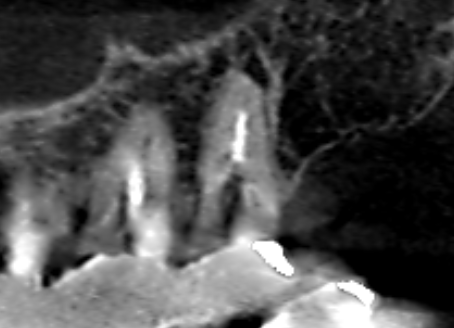

上顎第二大臼歯の冠状断のCT画像です。

矢印の上顎第二大臼歯の口蓋根の先に膿の影がみられます。根の先まで根管充填が届いていないのが分かります。